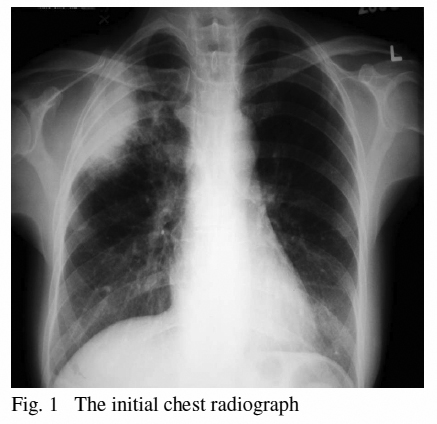

Her baseline blood tests revealed mild elevation of white cell count with neutrophilia. A course of Augmentin was given empirically and her symptoms subsided for several months. There was no radiological improvement in her follow up visits (Fig. 2), and her dry cough persisted.